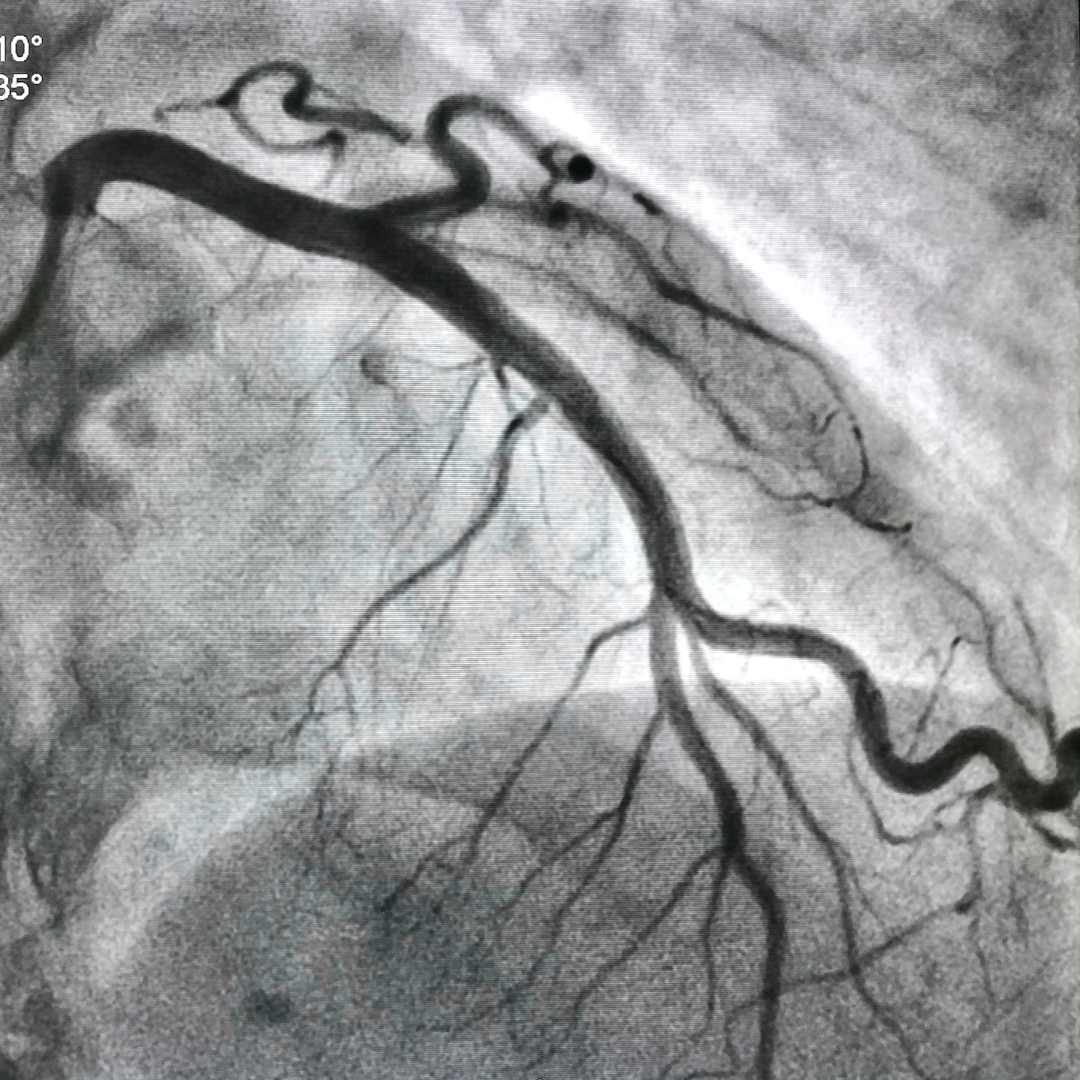

Angiography

Cardiac catheterisation is an invasive diagnostic procedure that helps doctors see blockages in heart arteries and understand the structure and function of the heart.